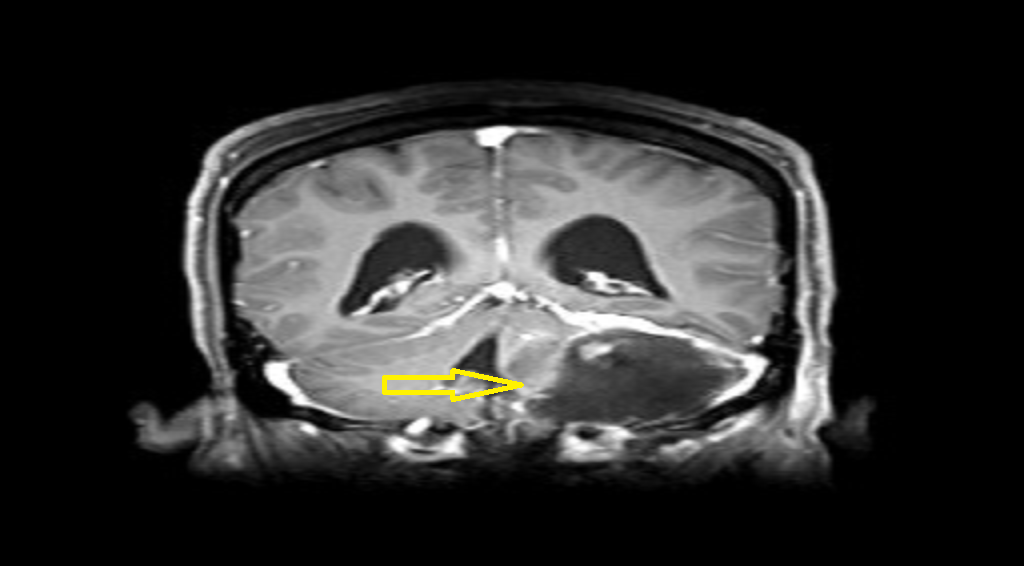

■ 袁女士颅内肿瘤位于左侧桥小脑角区,约6*4*4cm大小,占位效应明显,手术指征明确,其颅内肿瘤与周围血管及神经包裹密切,且体积巨大,经过长达六小时手术,肿瘤被顺利切除。

(术前)